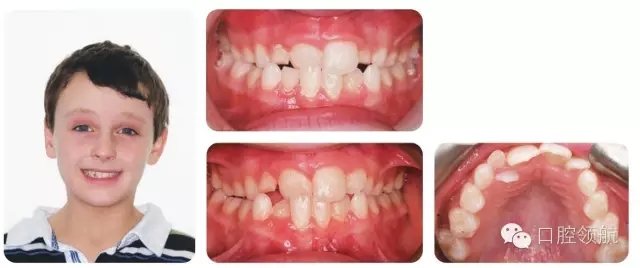

8歲的男性患者,處于混合牙列期,圖2.17上圖是當(dāng)時(shí)的咬合像,下圖是1年后的咬合像(正面和牙合面)。

圖2.17

I類切牙關(guān)系,UR1反。上下牙列均有擁擠,UR2腭側(cè)錯(cuò)位。